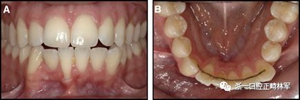

臨床檢查顯示固定保持器完好,弓絲沒有斷裂(圖13)。在下頜右側(cè)中切牙唇側(cè)和鄰近側(cè)切牙的舌側(cè)注意到有牙齦退縮。這些牙齒在退縮方向上存在顯著的扭矩差異。下頜的左側(cè)尖牙頰側(cè)錯(cuò)位,而右側(cè)尖牙舌側(cè)傾斜。三維射線照片證實(shí)了下頜右側(cè)尖牙面?zhèn)妊啦酃菃适?,右?cè)中切牙的喪失程度較輕。右側(cè)側(cè)切牙根也從舌側(cè)骨面上扭轉(zhuǎn)出來(圖14)。

圖13.粘合到尖牙和切牙上的柔性螺旋弓絲保持器,伴有牙齦退縮和附著喪失,中切牙之間嚴(yán)重的扭矩差異以及兩顆尖牙的橫向移動和扭矩。牙周問題和牙齒移動的嚴(yán)重程度均為牙周正畸聯(lián)合治療的指征:A,正面視圖; B,咬合面視圖。